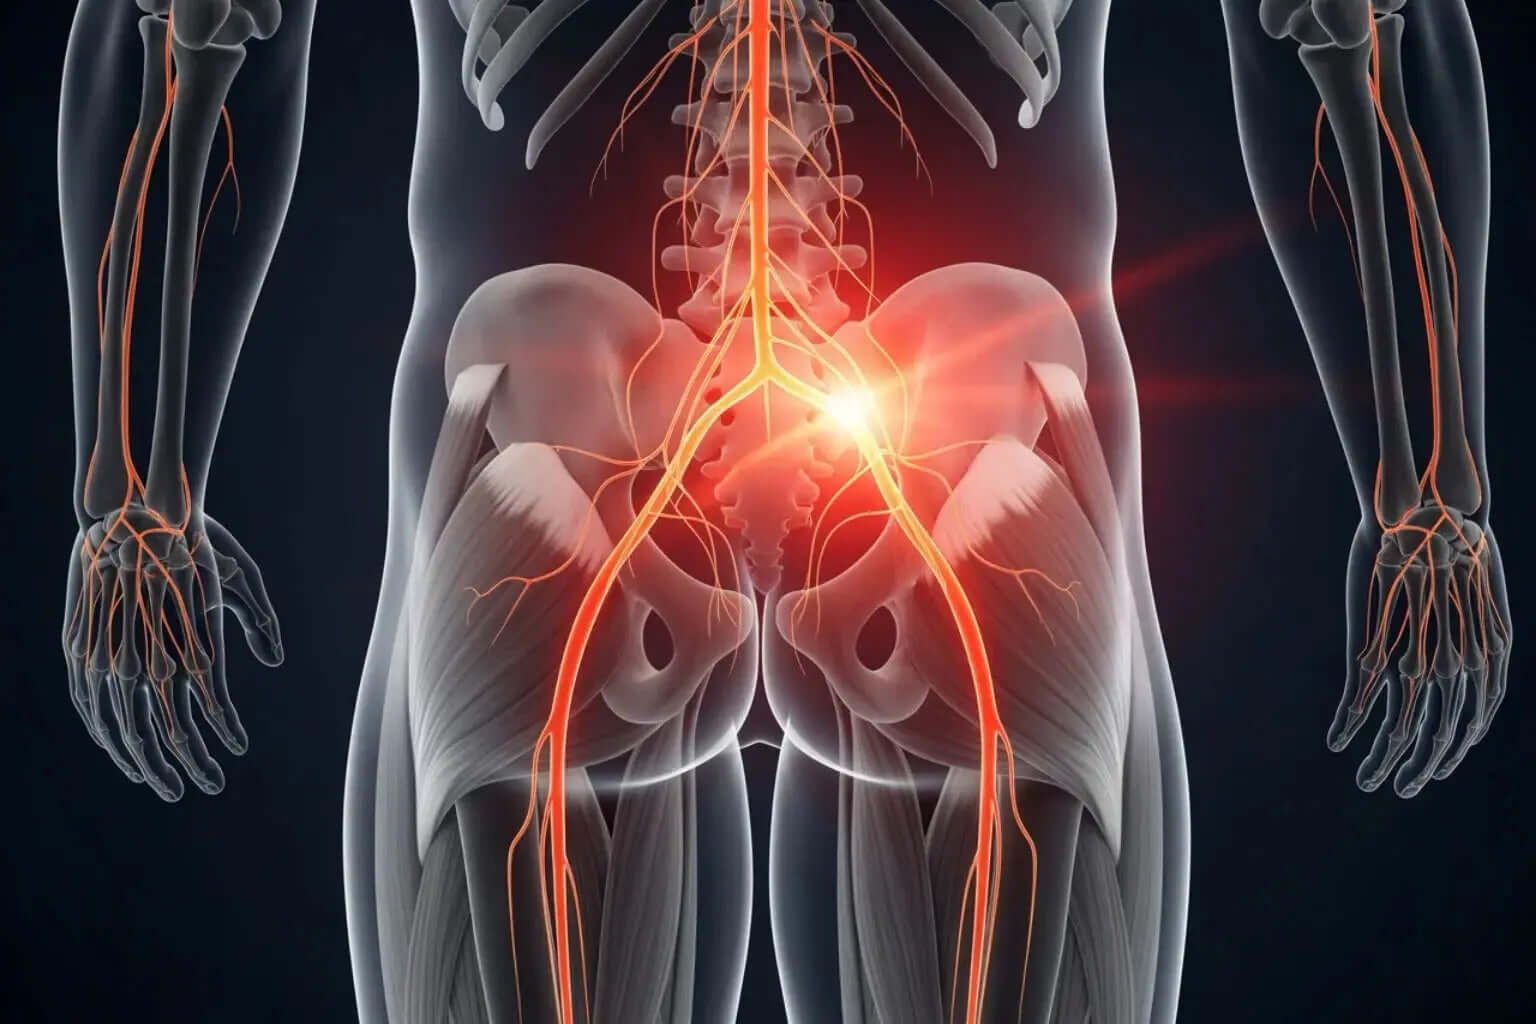

From sore muscles to nerve discomfort, we break down causes

and share expert-backed relief strategies.

A – Z Guide to What Causes Sciatica